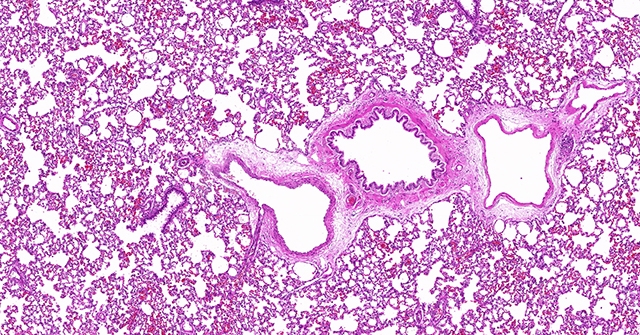

HE染色的原理和意义

染色是一种常见的化学实验技术,用于在生物学研究、医学诊断、组织学研究等领域中显示和区分细胞或组织的结构和成分。其中,常用的一种染色方法是使用可溶于水的染料将细胞或组织中的特定结构染色,从而使其能够被显微镜观察和分析。在这个过程中,一种被广泛使用的染料就是“HE染料”。

“HE染料”的全称是“Hematoxylin and Eosin”,即“血红木素和苏木精”。它由两种染料组成,分别是“hematoxylin”和“eosin”。这两种染料有着不同的性质和作用,在染色过程中发挥着重要的作用。

“hematoxylin”,它是从血红木树皮中提取得到的天然染料。它具有亲和力强、专一性好的特点,对细胞核和酸性成分具有较强的亲和力。在染色过程中,hematoxylin能够与细胞核内的DNA结合,使其呈现出蓝色或紫色的颜色。这使得我们能够清晰地观察到细胞核的形态、数量和位置,从而进行细胞结构和组织构成的分析。

“eosin”则是一种酸性染料,它具有亲和力强、颜色鲜艳的特点。在染色过程中,eosin能够与细胞内的碱性成分结合,使其呈现出红色或橙色的颜色。这样,我们可以通过eosin染色来显示细胞质、细胞间质和胶原纤维等碱性成分,从而更全面地了解细胞和组织的结构和组成。

“HE染料”的使用它可以帮助我们清晰地观察和区分细胞核和胞质等细胞结构,为研究细胞功能和病理变化提供了基础。其次,通过HE染色,我们能够获得组织的整体结构和组成信息,了解组织的功能和病理变化,从而为医学诊断和疾病研究提供了重要依据。此外,HE染色也被广泛应用于药物筛选、生物工程等领域,帮助科学家们更好地了解和探索生物体的奥秘。它的使用不仅加深了我们对生物体的认识,还为各个领域的研究提供了强有力的工具和手段。